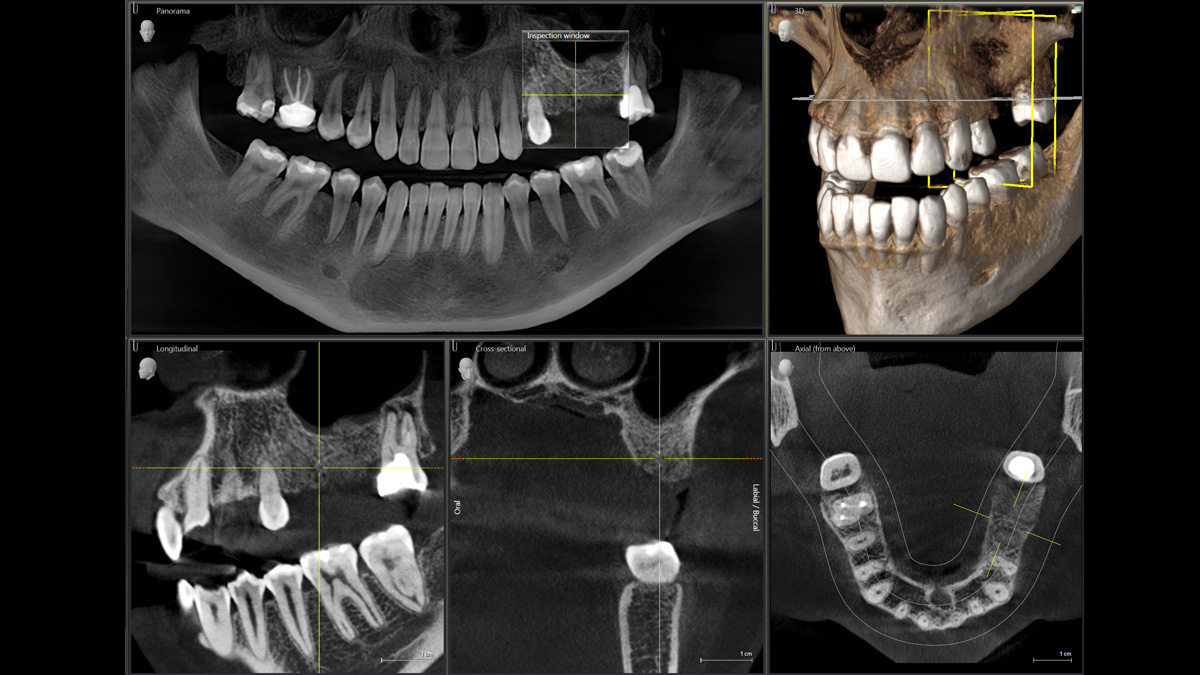

Der 2D/3D Power Performer Orthophos SL ist eine großartige Wahl für alle, die einfach mehr wollen. Der integrierte Direct Conversion Sensor (DCS) wurde für anspruchsvolle Bildqualitätsstandards entwickelt und bietet detaillierte Daten. Der intelligente Autofokus liefert automatisch fokussierte Panoramabilder mit hervorragender Gesamtschärfe. Orthophos SL bietet höchsten Bedienkomfort durch automatische Positionierung, eine anwenderfreundliche, intuitive Bedienung mit dem EasyPad und ein individuell einstellbares Umgebungslicht für ein exklusives Erscheinungsbild.

Mit dem Low Dose-Modus erhalten Sie 3D-Bilder im Dosisbereich einer 2D-Röntgenaufnahme. Im HD-Modus werden während eines einzelnen Umlaufs mehr als 800 Einzelbilder aufgenommen und zu einem 3D-Volumen mit bis zu 80 μm zusammengeführt. Der Vorteil für Sie: rauschärmere Aufnahmen in hoher Auflösung

Ein breites Spektrum an Volumengrößen für verschiedene diagnostische und klinische Anforderungen von Ø 5 × 5,5 cm bis Ø 11 × 10 cm